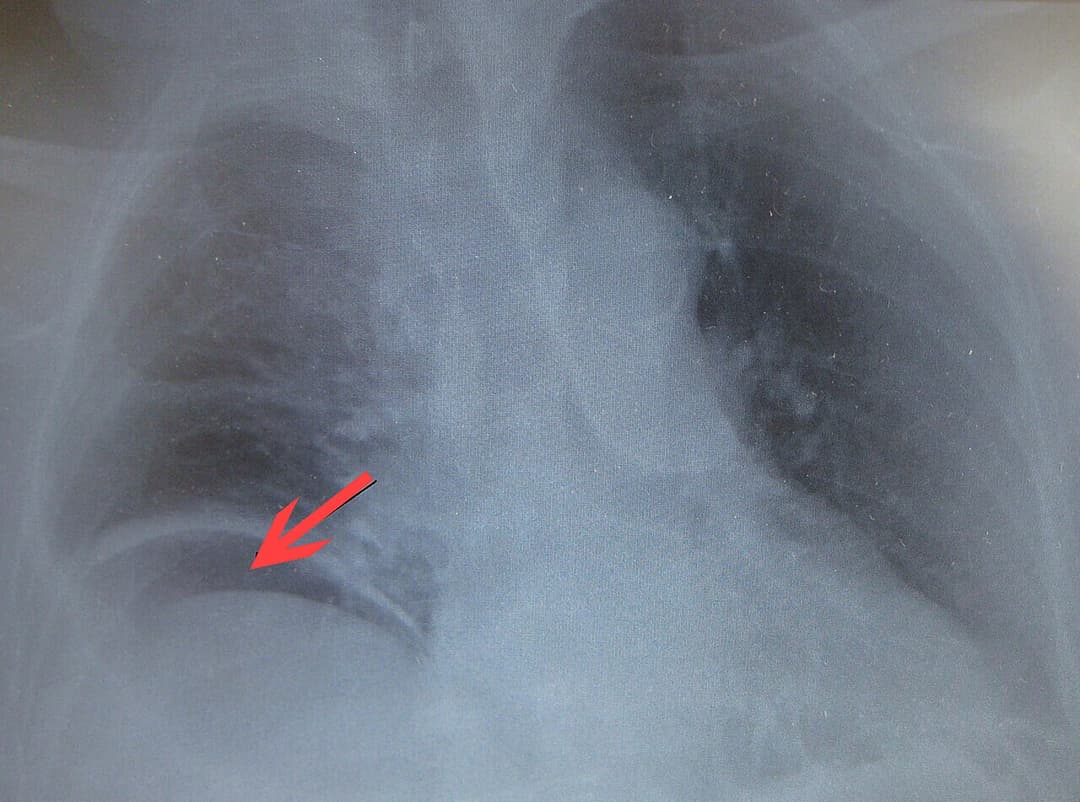

Gastrointestinal perforation, also known as ruptured bowel, is a hole in the wall of part of the gastrointestinal tract. The gastrointestinal tract includes the esophagus, stomach, small intestine, and large intestine. Symptoms include severe abdominal pain and tenderness. When the hole is in the stomach or early part of the small intestine, the onset of pain is typically sudden while with a hole in the large intestine onset may be more gradual. The pain is usually constant in nature. Sepsis, with an increased heart rate, increased breathing rate, fever, and confusion may occur. The cause can include trauma such as from a knife wound, eating a sharp object, or a medical procedure such as colonoscopy, bowel obstruction such as from a volvulus, colon cancer, or diverticulitis, stomach ulcers, ischemic bowel, and a number of infections including C. difficile. A hole allows intestinal contents to enter the abdominal cavity. The entry of bacteria results in a condition known as peritonitis or in the formation of an abscess. A hole in the stomach can also lead to a chemical peritonitis due to gastric acid. A CT scan is typically the preferred method of diagnosis; however, free air from a perforation can often be seen on plain X-ray. Perforation anywhere along the gastrointestinal tract typically requires emergency surgery in the form of an exploratory laparotomy. This is usually carried out along with intravenous fluids and antibiotics. A number of different antibiotics may be used such as piperacillin/tazobactam or the combination of ciprofloxacin and metronidazole. Occasionally the hole can be sewn closed while other times a bowel resection is required. Even with maximum treatment the risk of death can be as high as 50%. A hole from a stomach ulcer occurs in about 1 per 10,000 people per year, while one from diverticulitis occurs in about 0.4 per 10,000 people per year. Signs and symptoms may include a sudden pain in the epigastrium to the right of the midline indicating the perforation of a duodenal ulcer, while a gastric ulcer perforation reveals itself by burning pain in epigastrium, with flatulence and dyspepsia.